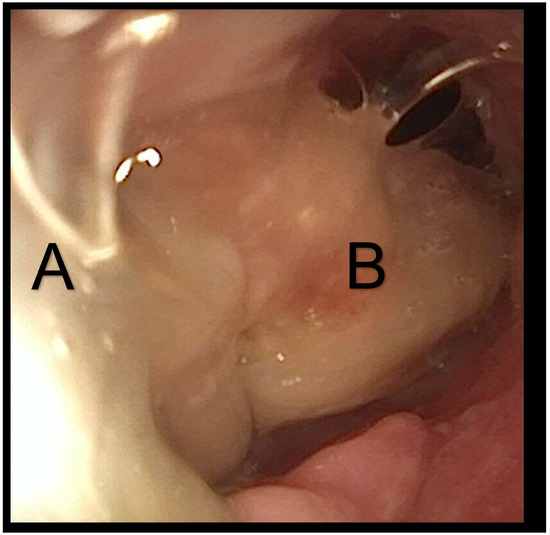

Bronchoscopic examination revealed a large mucus plug that obstructed the entire tracheal lumen and was distal to the tracheostomy tube (Figure 4). The mucus crust was larger than the tracheostomy tube, making retrieval very challenging. During extraction attempts, the plug shifted position and was found in both main bronchi. The patient experienced desaturations, necessitating the insertion of a cuffed tracheostomy tube and increased ventilatory support. Under bronchoscopic guidance, a large intratracheal suctioning device was utilized to successfully remove the large mucus plug (Figure 5). After thorough tracheal cleaning, the patient’s oxygen saturation improved to 95%. A subsequent bronchoscopy showed no significant pathology or residual mucus.

Figure 5. Withdrawal of the mucus plug. The opening made by the tracheostomy is visible on the left side (A). The cannula has been pulled back. A portion of the mucus plug remains within the trachea (B).